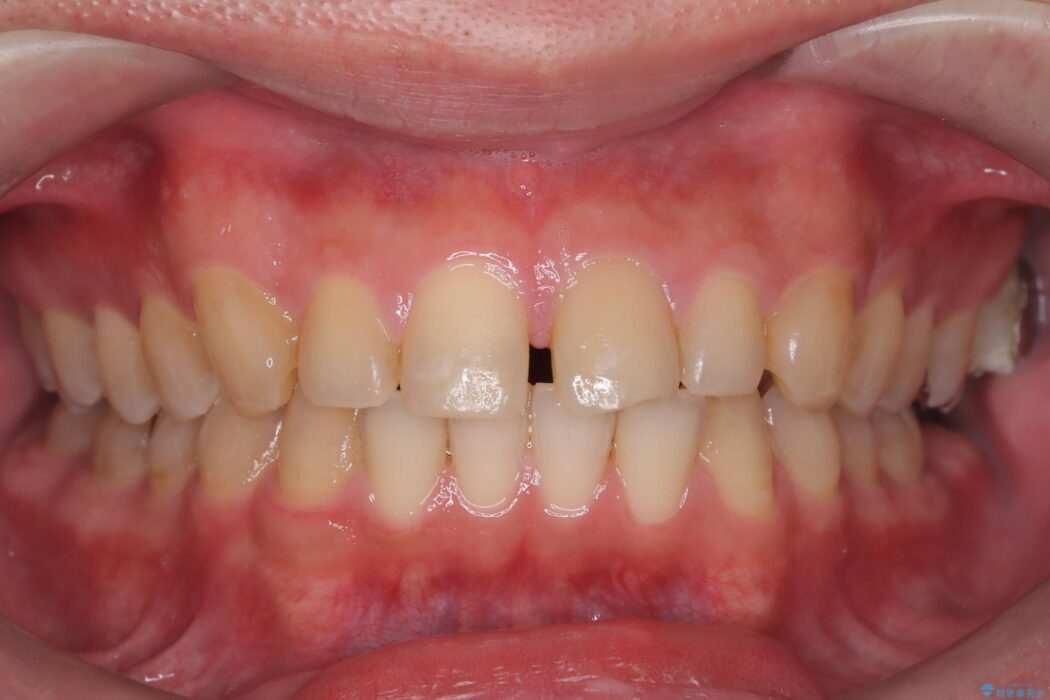

歯の隙間とデコボコ、シザーズバイトも改善され、咬み合わせや見た目が整い、患者様にも大変ご満足いただけました。